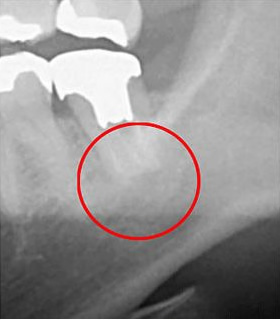

次の画像は、同じ患部をCTとレントゲンで撮影した画像です。

上の写真をご覧ください。左側がCTによるもので、右側がレントゲンで撮影されたものです。赤丸で囲まれた部分にご注目ください。左のCT画像では黒い影が見えます。これは炎症が起こっていることを示していますが、右のレントゲン画像ではその影が確認できません。

このように、もしレントゲンだけで診断していた場合、この炎症を見逃すリスクがあります。結果として、気づかない間に炎症が悪化し、最悪の場合抜歯が必要になることも考えられます。当院では、こうしたケースを防ぐために、CTによる詳細な診断を行っています。